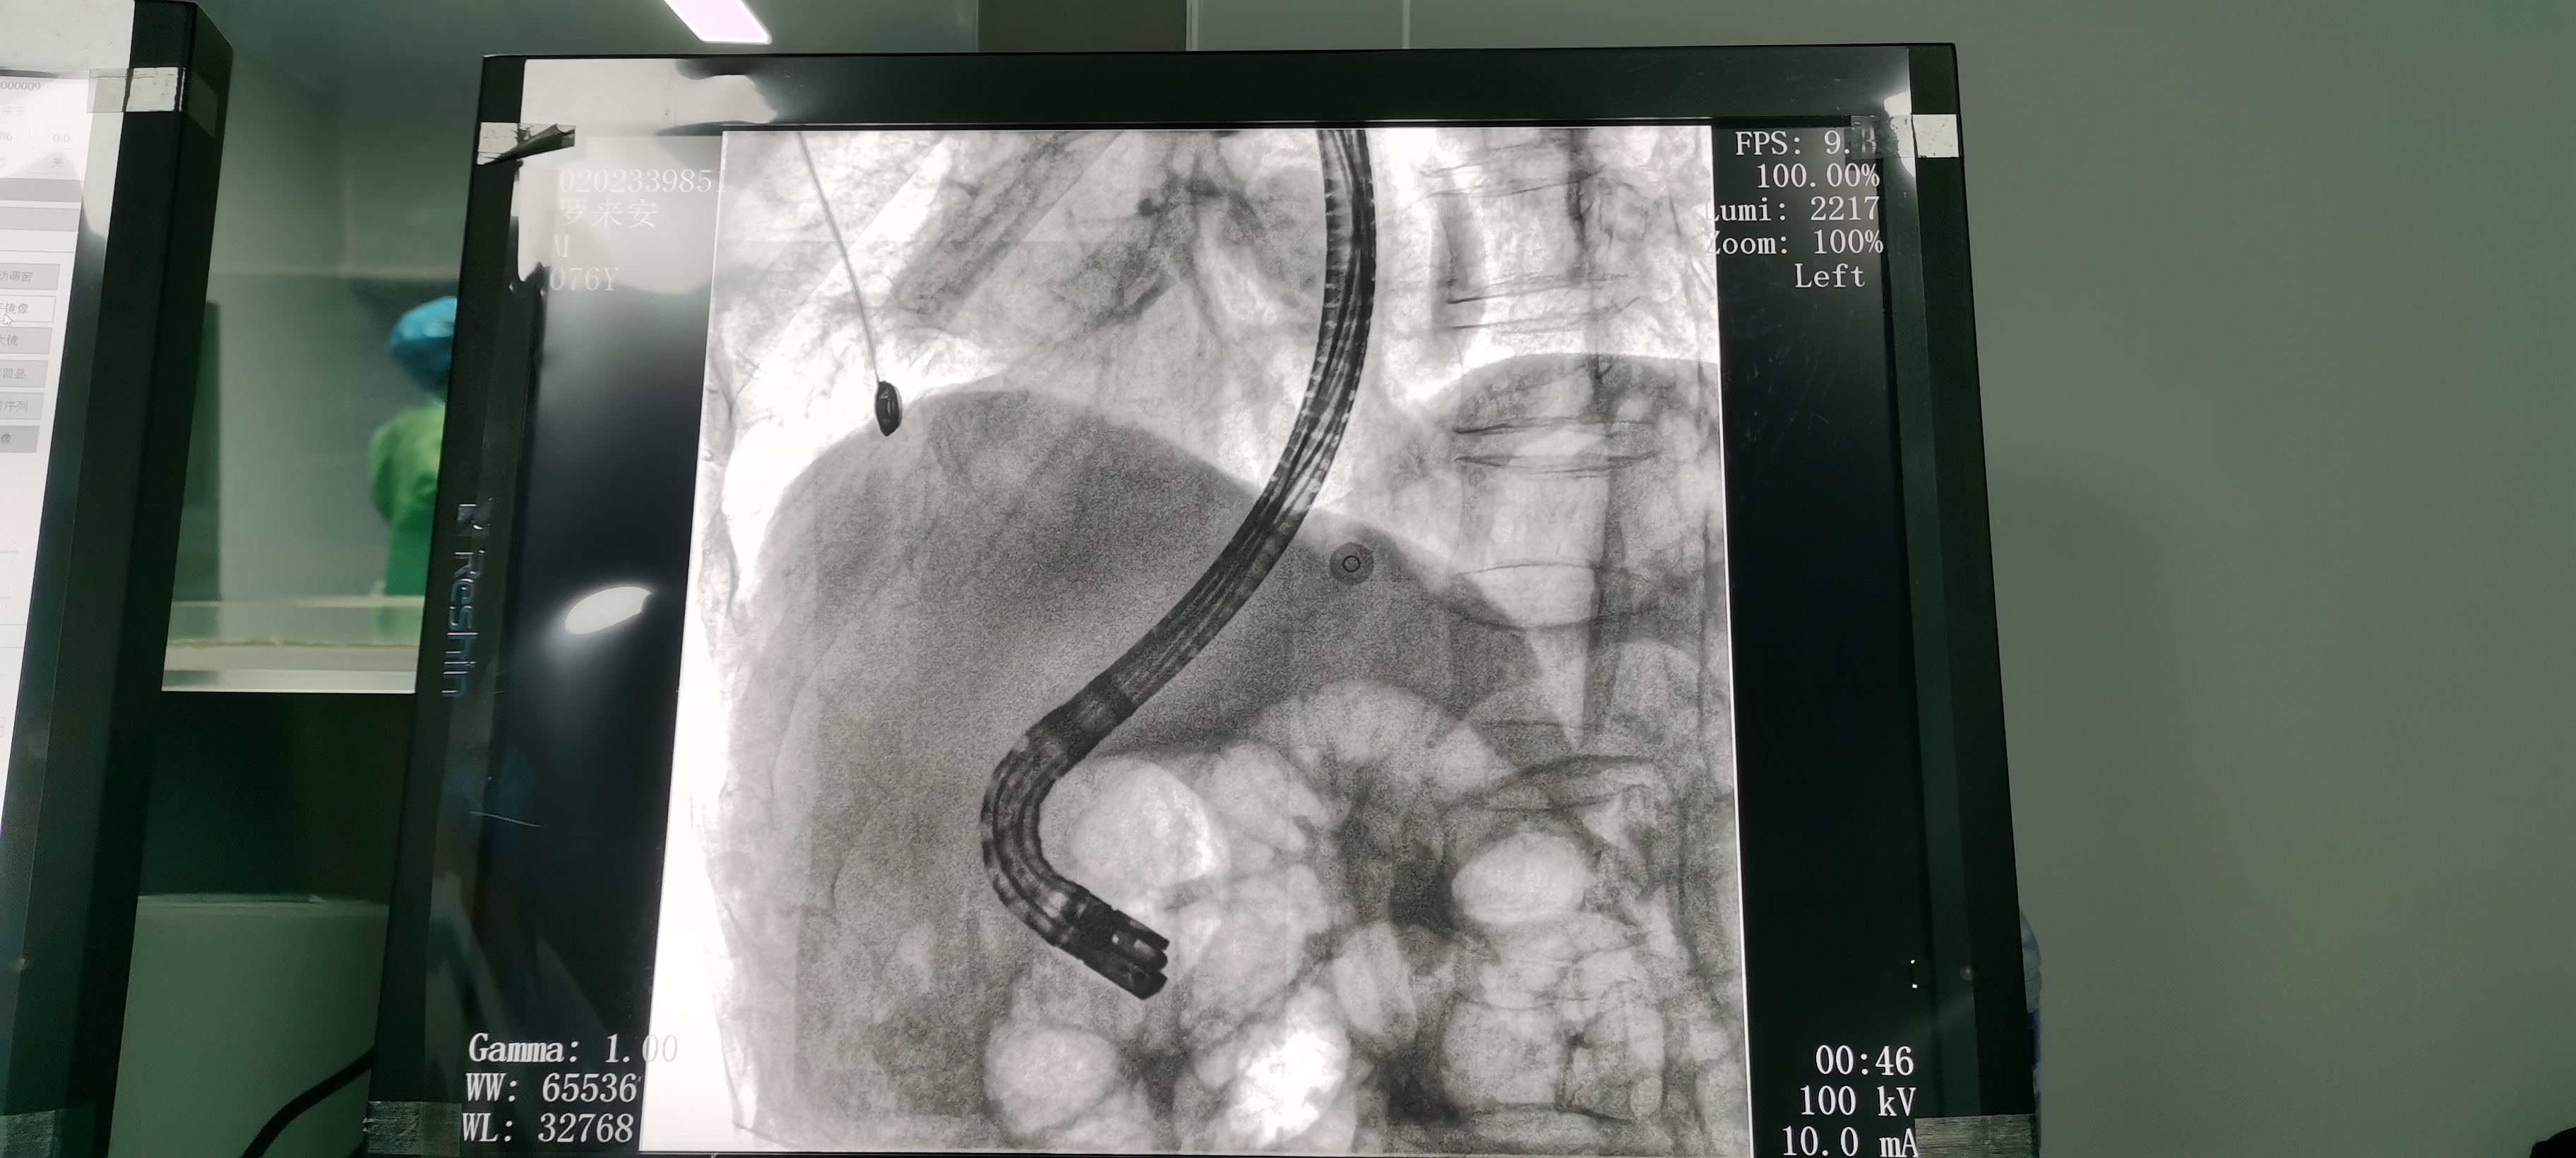

Intraoperative Fluoroscopy

ERCP is known as "the brightest pearl in the crown of digestive endoscopy". The doctor inserts an endoscope into the patient's mouth, enters the duodenum and finds the duodenal papilla, inserts a catheter through the endoscope and injects a contrast agent into the bile ducts, and then observes the bile ducts and the pancreatic ducts under X-ray fluoroscopy to visualize the bile ducts and the pancreatic ducts, so as to carry out the corresponding treatments. After years of clinical practice, ERCP has become an important method for clinical diagnosis and treatment of biliopancreatic diseases.EST (endoscopic duodenal papillary sphincterotomy), on the other hand, is developed on the basis of ERCP, which, as a minimally invasive surgery, can be used for safe, rapid and effective treatment of diseases such as choledochal stones.

Intraoperative ERCP images